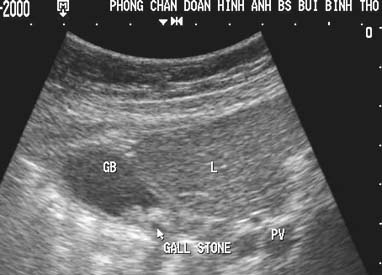

Image echographique

:

C'est la technique de la premier de l'intention pour

explore de calcul vesiculaire , sa sensibilite et sa specifilite

est tres bonne de donnee des signes direct ou indirecte des

voies biliaire intrahepatique( VBIH ) ou des voie biliaire

pricipale ( VBP) . Images echographique direct de

calcul vesiculaire est image hyperechogene en forme C

inverse ,avec de vide aoustique posterieure , sa nombre , la

taille est varie .Localisation peut mobilisee quand on a change

position du maladie " rolling stone sign "

Petite calcule a

infundibulum de la vesicule biliaire . Coupe

echographique recurrent a hypochondre droit |

Calcul vesicule biliaire :

Image hyperechogene de 10mm en C forme

avec espace de

vide ascoustique posterieure en voyant tres fine .

Image echographique du foie |